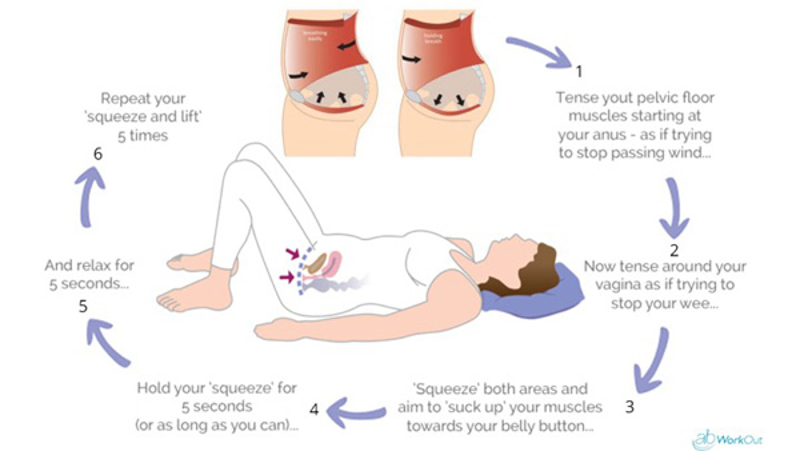

Read MoreEffect of physical therapy in urinary incontinence

Urinary incontinence is the complaint of involuntary loss [leakage] of urine. The condition occurs in both sexes but more frequent in women. Incontinence in women is related to the dysfunction of bladder or pelvic floor muscles which often arise during or after pregnancy or at the time menopause. Long term cough, constipation, overweight, pelvic surgery […]